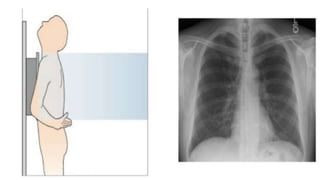

Posterior-anterior (PA) Position

• The standard position for obtaining a routine adult chest radiograph

• Patient stands upright with the anterior wall of chest placed against

the front of the film

• The shoulders are rotated forward enough to touch the film, ensuring

that the scapulae do not obscure a portion of the lung field

• Usually taken with the patient in full inspiration

• The PA film is viewed as if the patient is standing in front of you